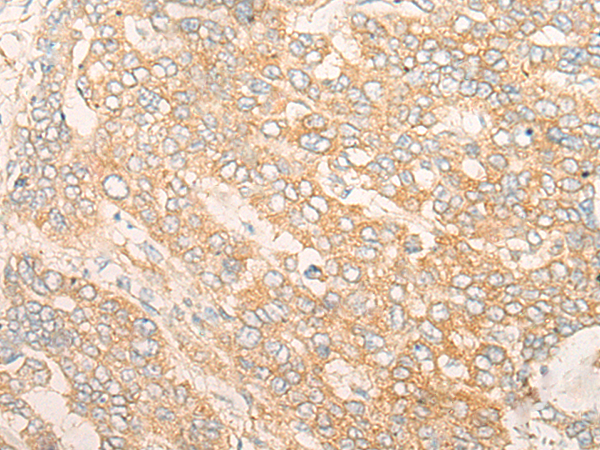

分类: 科研抗体货号: P06377别名: dgkd-2; DGKdelta应用: IHC反应种属: Human